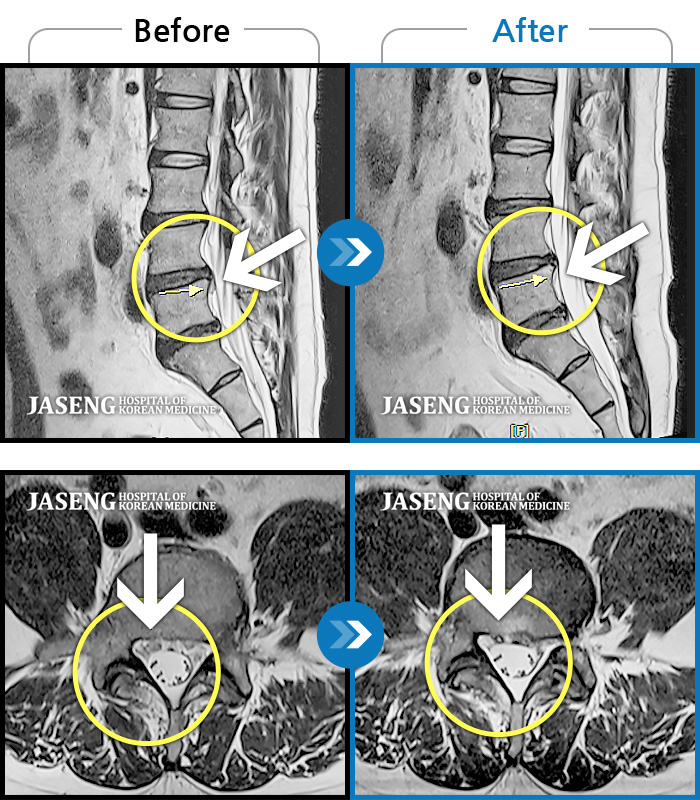

허리디스크

광주 · 김동은 원장

좌측 골반 및 종아리부터 발까지 이어지는 저림과 통증으로 내원하셨습니다.

촬영시기

2023.10.03 ~ 2025.08.14

2025.08.22